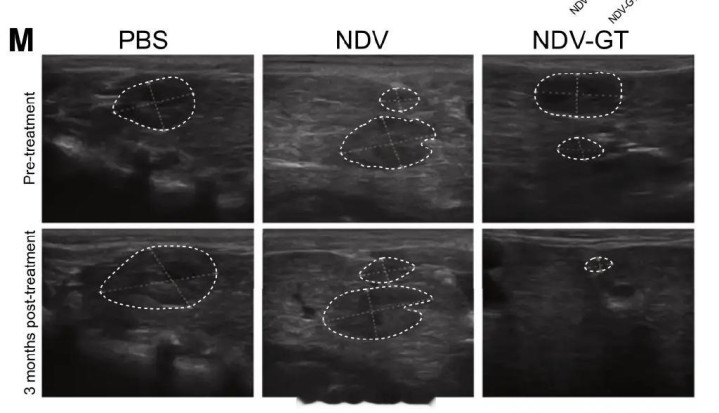

在猴子肝癌模型实验中,这种溶瘤病毒成功让肿瘤在3个月内完全消失,且没有严重副作用。

彩超显示 NDV-GT 治疗后猴子肿瘤消退甚至消失